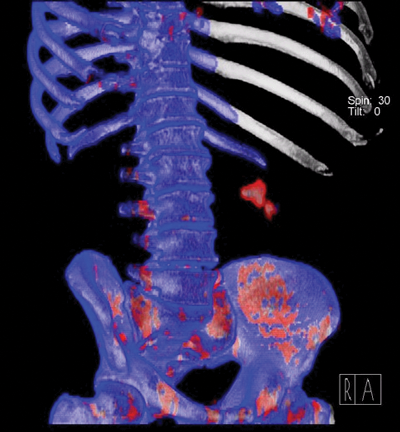

Figure 3: Uric acid calculus in the left kidney.

Figure 4: Non-uric acid calculus in the left kidney.

Interpretation of images

The CT scan needs to be interpreted as any CT, with the radiologist commenting on size and position of renal calculi as well as any signs of obstruction. The dual-energy stone algorithm analyses the attenuation values of any calculi at both energy levels and a further image is acquired. Figures 3 and 4 show the final image produced by the CT, using the software for stone composition. Figure 3 demonstrates a uric acid calculus, as shown in red, and Figure 4 shows a non-uric acid calculus, shown in blue. A mixed composition stone will contain both red and blue components.

A 59-year-old male patient who weighed 200kg presented with renal impairment and underwent unenhanced CTKUB. This showed bilateral renal calculi and a right ureteric stone with hydronephrosis. Retrieval of the right ureteric stone was going to be difficult due to patient weight and a dual-energy CT was therefore performed to ascertain if the calculus may be amenable to medical management. CT showed the right ureteric calculus was composed of uric acid (seen as red following stone algorithm), and the patient was treated medically rather than undergoing high-risk invasive treatment. Three months later the patient underwent repeat CTKUB, which demonstrated that the right ureteric stone had decreased in size and the hydronephrosis had improved.